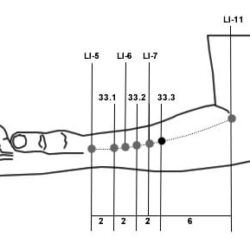

אזור DT

DT.01 – מפריד ענף עליון Fēn Zhī Shàng 分枝上 DT.02 – מפריד ענף תחתון Fēn Zhī Xià 分枝下 DT.03 – שבעת הכוכבים Qī Xīng七星 DT.05 – שני עוף החול Shuāng Fèng 雙鳳 DT.08 – ענף התמצית Jīng Zhī 精枝 DT.09 – יער המתכת Jīn Lín 金林 DT.15 – שלושת הנהרות Sān Jiāng 三江 DT.17 – לשגר מעלה לשמיים Chōng Xiāo 衝霄